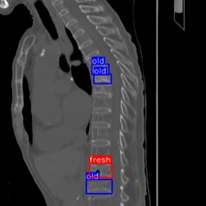

研究團隊蒐集自大林慈濟醫院的10,305張脊椎CT影像,處理後選用5,631張側面切面影像進行AI訓練與測試,導入YOLOR深度學習架構,並結合三種影像特徵模型(MobileViT、EfficientNet_NS與CSPDarknet53)與Involution技術進行優化,最後透過集成學習方式整合各模型優勢,成功建立準確率高達93.4%的AI系統。

CT影像AI判讀系統 AI幫你辨識清新舊骨折 準確率高達93.4% 03

CT影像AI判讀05